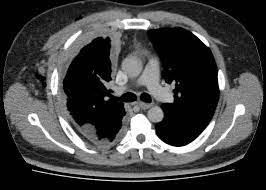

Eventos adversos neurológicos relacionados con inhibidores de puntos de control inmunológico en España

La mayoría de los eventos adversos relacionados con el sistema inmunológico neurológico afectaron al SNC y fueron negativos para anticuerpos. La presencia de miocarditis, miastenia y miositis, de encefalopatía sin cambios inflamatorios o de cáncer de pulmón fueron predictores independientes de muerte. The Lancet Neurology, diciembre de 2023.